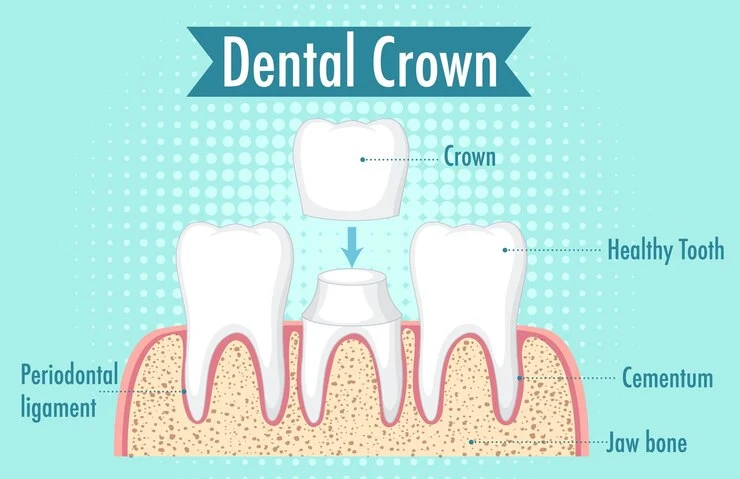

Dental crowns and bridges are restorative dental treatments. A crown is a cap placed over a damaged tooth to restore its shape, size, strength, and appearance. A bridge replaces one or more missing teeth by anchoring artificial teeth to adjacent natural teeth or implants. Both enhance function, aesthetics, and oral health.

- Dental crowns and bridges serve as versatile solutions for various dental issues, including repairing cracked or fractured teeth, filling gaps left by missing teeth, and improving the appearance of misshapen or discolored teeth.

- Crowns and bridges are crafted from a variety of materials such as porcelain, metal alloys, or a combination of both, offering options that balance aesthetics, durability, and cost to meet individual patient needs.

- Dental crowns help protect weak or damaged teeth from further decay or fracture, preserving their integrity and preventing the need for extraction.